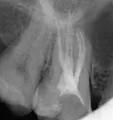

У меня была, в коренном зубе снизу - дырка без пломбы, пломба выпала - была временной. Вот так ходила несколько месяцев. В итоге: последнее время стал болеть зуб и я его, случайно, повредила твердой пищей, там и до нерва похоже дошло. И вот я сходила к врачу, она запломбировала зуб с лекарством и назначила лечение, через пятнадцать дней, примерно. Изначально зуб не болел и неприятных ощущений не было, но спустя сутки стал болеть, и со временем все сильнее. Сильное ощущение сдавленности в зубе со всех сторон, больно жевать и при слабом надавливании больно.

Это состояние норма при лечении хронического воспаления, за счёт лекарства происходит локализация воспаления и отсюда боль, также возможна небольшая припухлость. При сильных болях и припухлости покажитесь лечащему врачу, также возможно принятие антибиотиков по согласованию с лечащим врачом.